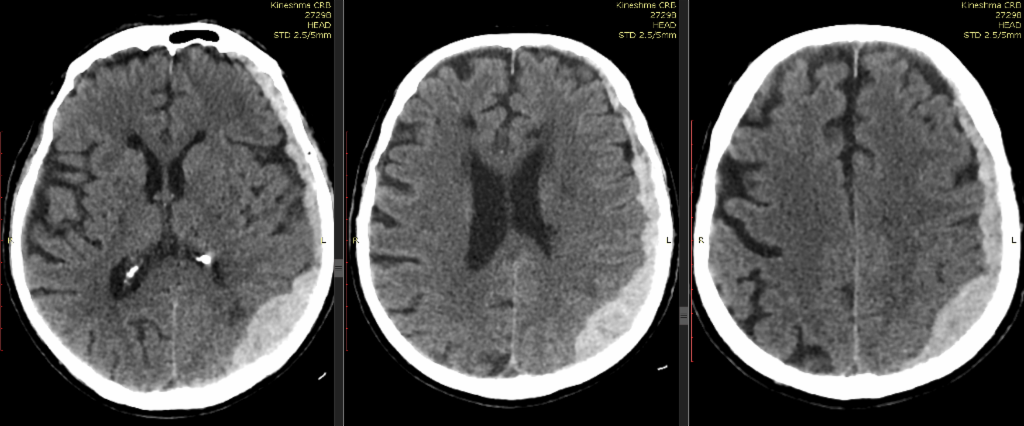

Инсульт удаление гематомы